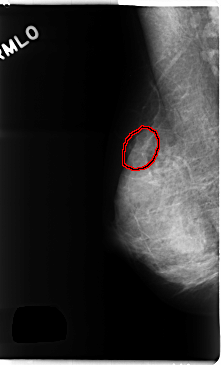

C_0257_1.RIGHT_MLO

FILE: C_0257_1.RIGHT_MLO.OVERLAY

TOTAL_ABNORMALITIES 1

ABNORMALITY 1

LESION_TYPE MASS SHAPE OVAL MARGINS OBSCURED

ASSESSMENT 4

SUBTLETY 3

PATHOLOGY BENIGN

TOTAL_OUTLINES 1

BOUNDARY